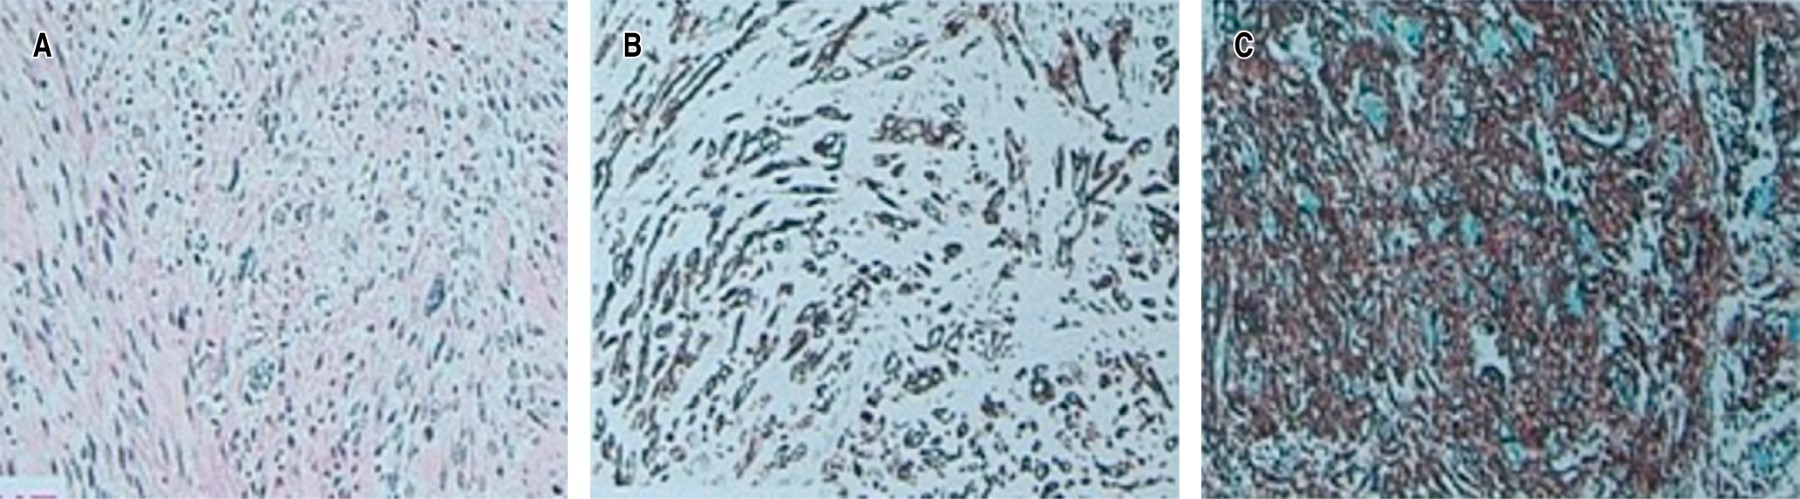

El leiomiosarcoma es un tipo de cáncer que se origina en las células musculares lisas del útero, el tracto gastrointestinal y otros tejidos blandos. La rara aparición del leiomiosarcoma en la cavidad oral se ha correlacionado con la escasez de estructuras musculares lisas en esta localización. Se trata de un tumor de tejidos blandos raro y agresivo que representa aproximadamente 5-10% de todos los sarcomas de tejidos blandos, y sólo 3% de estos tumores se producen en la región de la cabeza y el cuello. El diagnóstico diferencial puede ser problemático. El aspecto físico puede confundirse con afecciones no malignas. El diagnóstico diferencial clínico de la lesión incluye los tumores glandulares (adenoma pleomórfico, carcinoma mucoepidermoide y carcinoma adenoide quístico) y los tumores mesenquimales. Relatamos un caso de leiomiosarcoma maxilar en un paciente de 86 años que fue sometido a una resección tumoral y tuvo como complicación la necrosis casi completa del retallo quirúrgico. Gracias a la terapia con láser, logramos la curación completa del colgajo y el implante y la rehabilitación dental con carga inmediata.

Figura 1